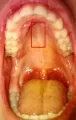

Здравствуйте, мне 60 лет, зубы все свои, 2 дня назад воспалилась левая сторона верхнего неба, появились две, если их так можно назвать язвочки размером с 1 мм середина красно-розовая и к низу от зубов беловатый налет, есть не мешают, расположены ближе к задним зубам и зубы, около которых они находятся ноют, один из них запломбирован. Днем боли почти не чуствую, а ночью даже не дают спать, пока не выпью анальгин. Сейчас воспаление начало перемещаться к передним зубам, а ближе к голу появились точки похожие на укол.

Добрый день. Сложно сказать, я считаю, что проблема связана с воспалением на верхушках корней. Необходимо проделать рентген-снимки для анализа. Рекомендую не тянуть и обратиться к врачу.